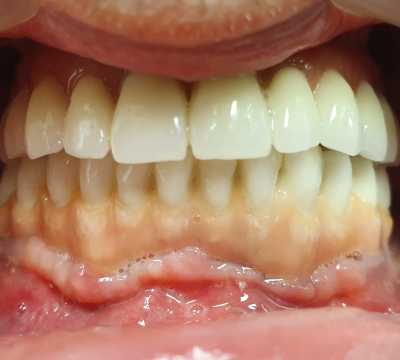

S-au inserat 10 implanturi dentare la nivel maxilar si 7 la nivel mandibular, pe baza carora s-au realizat protezari fixe metalo-cermice mandibular si ceramica pe zirconiu la nivel maxilar.

N.B. Cel de-al 7-lea implant mandibular a fost inserat la o luna distanta de la interventia initiala- defectul osos local fiind prea avansat pentru inserarea implantului in acelasi timp operator.

Implanturile dentare oferă un suport pentru dinții artificiali, eliminând orice neplăceri provocate de aceștia. În plus, implanturile îmbunătățesc masticația și vorbirea. Acestea vă oferă o forță de masticație mai mare, conservarea dinților naturali rămași, confort sporit și estetică superioară.